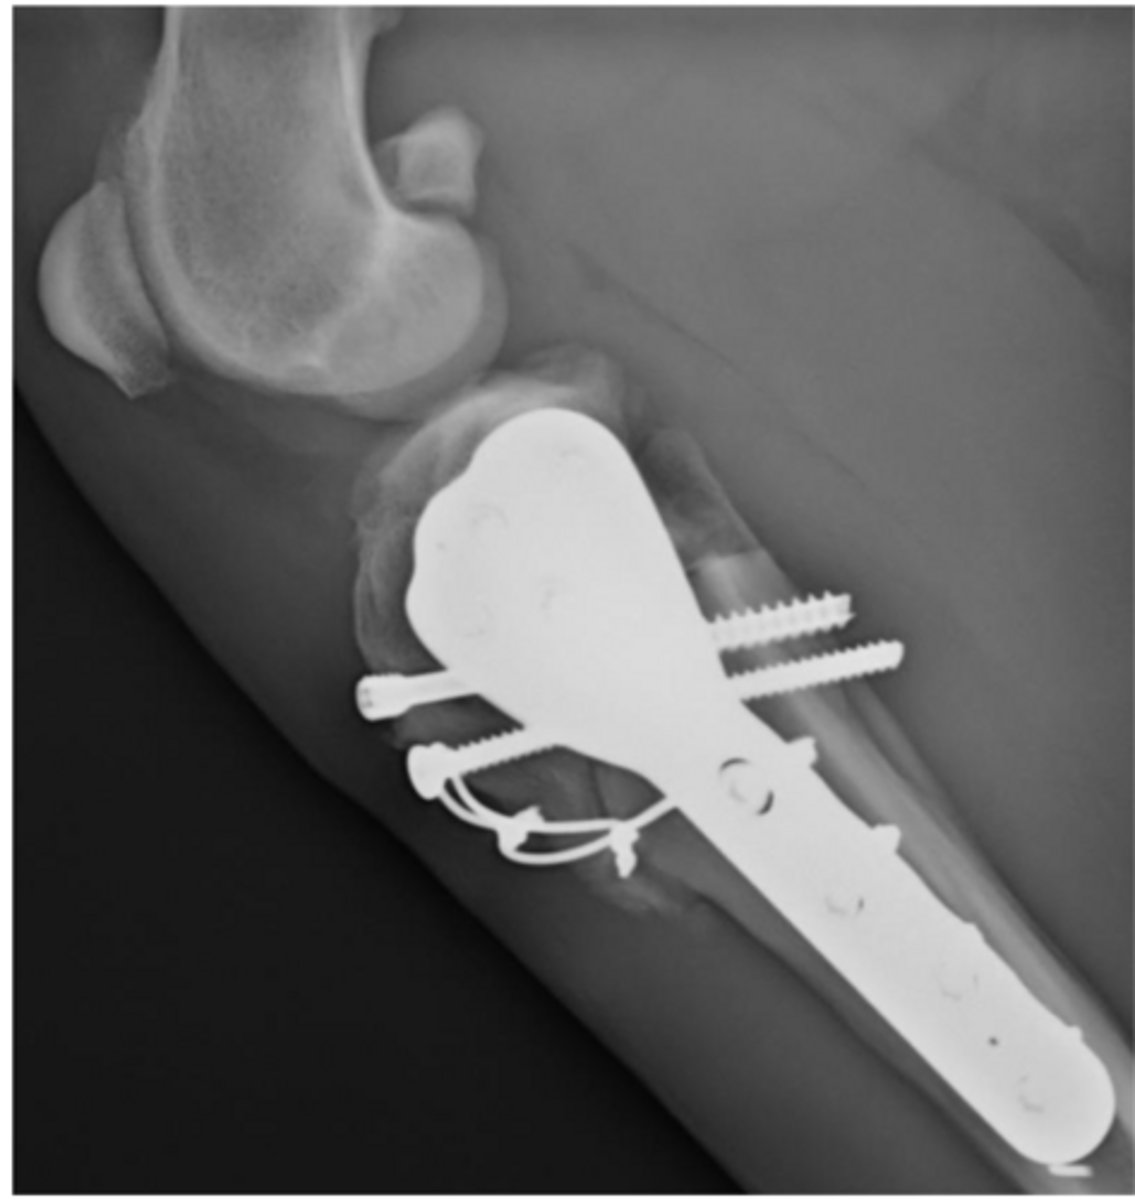

CORA (CBLO) center rotation and angulation of tibia to correct angular limb deformity

what procedure is shown here